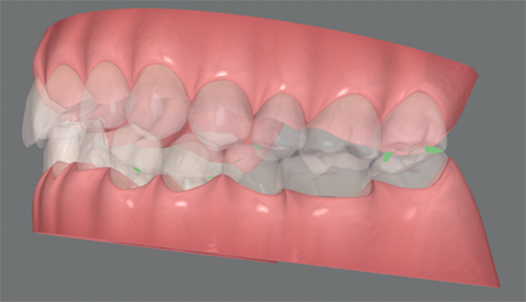

今回のケースでは、以下のようなシミュレーションを組んで治療しました。

ポイントは先に挙げた3つの問題の解決です。

1.歯全体で噛めず、奥歯だけが強く当たる状態になっていた

2.前歯の凸凹の影響で、歯本来の機能が働かなくなっている

3.上の歯列が右下がりになっている

治療後の写真は、以下のとおりです。

噛み合っている面に傾きがなく、床に対して真っすぐになりました。また、「真っすぐ正面を見てください」と伝えたときに、首が曲がらなくなりました。3Dデータを見ても、接触点(緑色と赤色)が全体に分散しました。